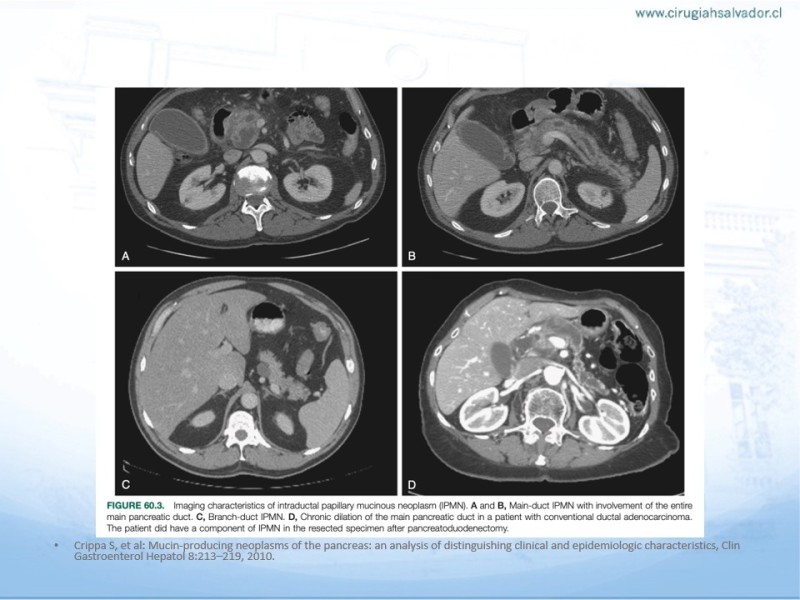

Tumores Pancreáticos no adenocarcinomas

Hepatobiliopancreático

| Autor: Dr. Matías Osorio Reyes